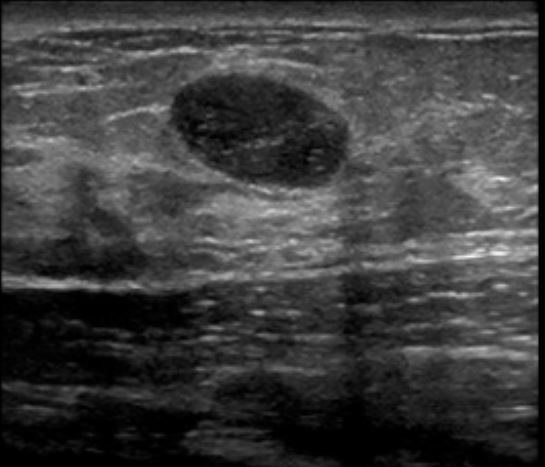

Q

Que característica de tumor esse USG sugere?

A

Benigno